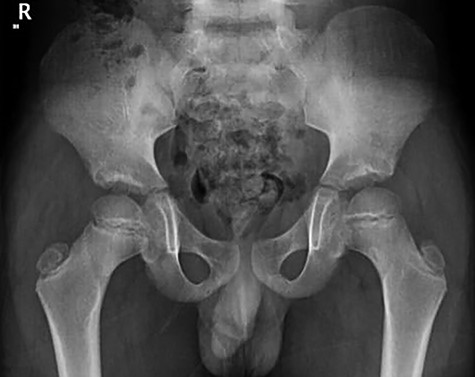

Follow-up of the case showed complete regression of the symptoms. Patient was full weight-bearing and performing daily activities with no pain, straight leg raises up to 90 degrees, Range of motion was fully painless with flexion 120 degrees, while extension, abduction and external rotation were 20, 40 and 35 degrees respectively (Figure 8, 9).

Follow-up X-ray showed regression of the lesion in the form of progression of the dense sclerosis of the defect of the left femur while the right femur neck lesion is barely visible (Figure 10) and advised for watchful waiting.